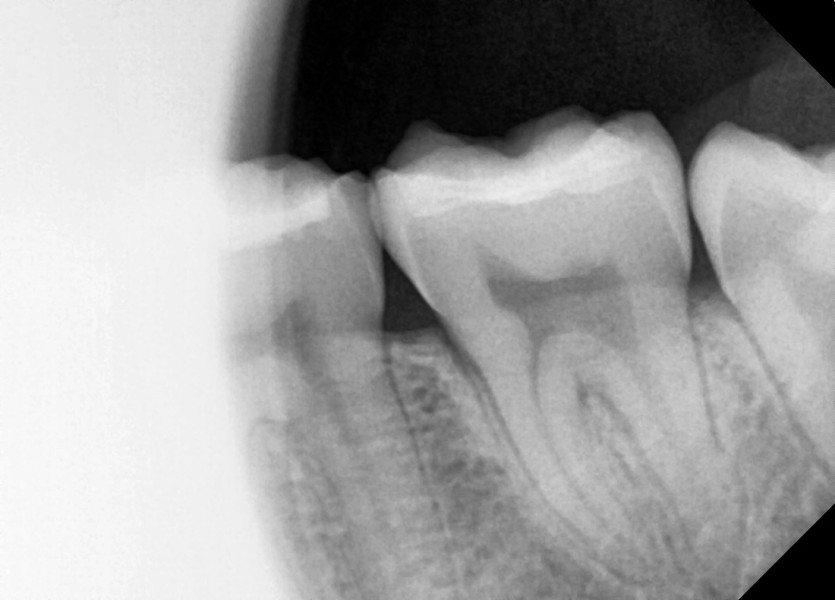

#38,48 사랑니 발치

구강 외과 전문의가 당일 발치했습니다.